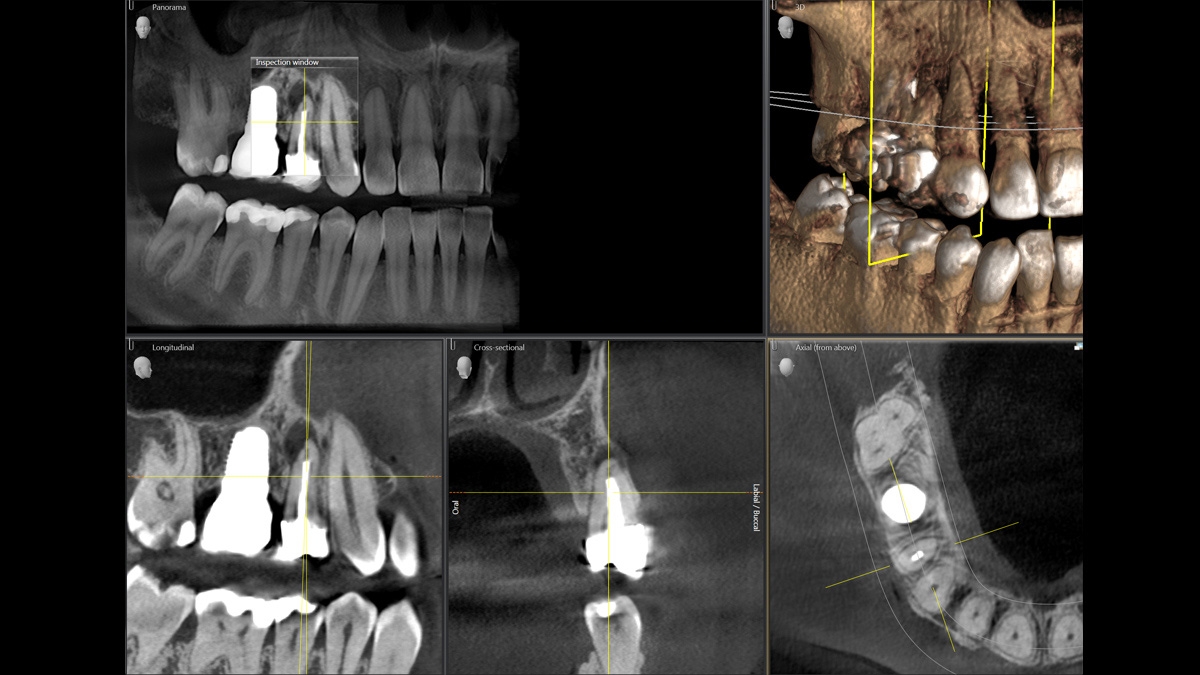

Gallery of Sample 3D Images

11 cm x 10 cm implant case

MARS – Metal Artifact Reduction Software

Metal artifacts are a challenge in 3D X-ray imaging. Radiopaque objects create shadowing and streaking effects during the three-dimensional reconstruction and as such interfere with the findings. MARS automatically reduces metal artifacts and facilitates the diagnosis.